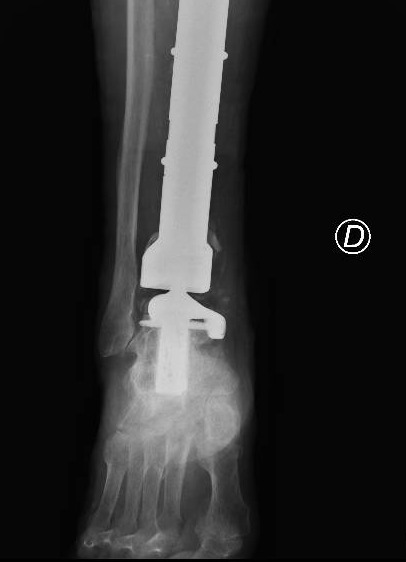

Il paziente veniva dunque trattato con una resezione del tumore con impianto di mega-protesi di tibia prossimale (cioè nell’area vicino al ginocchio). Ma i problemi non erano finiti. Dopo circa un anno dall’intervento, compariva una grave infezione della protesi impiantata e questo porta Mario a una serie di complessi interventi chirurgici, esitati con l’impianto di una protesi totale di gamba e di caviglia in titanio, rivestita in argento per proteggerlo dalle infezioni.

A distanza di sei anni, Mario torna dagli ortopedici del Gemelli per la comparsa di un dolore alla caviglia. Gli esami effettuati rivelano la rottura di una vite della protesi, a livello della caviglia. È necessario dunque sostituire questo pezzo, ma l’unico modo per farlo è facendo confezionare una protesi su misura (‘custom-made’). Gli ortopedici del Gemelli inviano la TAC di Mario all’Implantcast, una ditta specializzata di Buxtehude, una cittadina a sud ovest di Amburgo.

Basandosi sulla ricostruzione 3D della caviglia ‘bionica’ di Mario, i bioingegneri realizzano un “calco” della protesi custom-made con una stampante 3D, sul quale viene poi realizzata la protesi in titanio per l’impianto definitivo. Tutto è pronto per l’intervento al Gemelli che viene realizzato dal professor Carlo Perisano, professore aggregato dell’Università Cattolica del Sacro Cuore e dirigente medico presso la UOC di Ortopedia e Traumatologia di FPG, diretta dal professor Giulio Maccauro. Si tratta di un intervento unico nel suo genere, un esempio di come la medicina di precisione e personalizzata sia ormai entrata a far parte anche degli interventi chirurgici. Che dà i suoi frutti. A distanza di appena qualche giorno dall’intervento, Mario sta di nuovo in piedi sulla sua gamba ‘bionica’ arricchita di quest’ultimo gioiello tecnologico.

“Il paziente era stato sottoposto negli anni a diversi interventi chirurgici per il trattamento di un tumore osseo della tibia e delle successive complicanze che avevano compromesso anche le articolazioni del ginocchio e della caviglia – spiega il professor Perisano -. Nel 2019, è stato sottoposto a posizionamento di mega-protesi custom-made personalizzata di tibia totale ginocchio e caviglia, scongiurando così il rischio di una chirurgia demolitiva, ovvero dell’amputazione dell’arto, garantendo al paziente il ritorno alle normali attività quotidiane.

Le protesi personalizzate (o ‘custom-made’) rappresentano un’innovazione significativa in ambito ortopedico. Si tratta tuttavia di impianti costosi, proprio perché realizzati ‘su misura’, che vengono per questo riservati a casi particolari e selezionati. L’impiego di tali protesi ci consente di personalizzare l’intervento sulle specifiche esigenze del paziente, garantendo un’accurata riproduzione anatomica ed un elevato grado di recupero funzionale. Nel caso specifico, la realizzazione di una componente astragalica su misura ci ha consentito di revisionare l’attuale protesi di caviglia e ha permesso al paziente un precoce ritorno ad un livello funzionale normale”. La revisione con una protesi di caviglia custom made di una protesi totale di caviglia e tibia è un intervento finora mai descritto in letteratura.